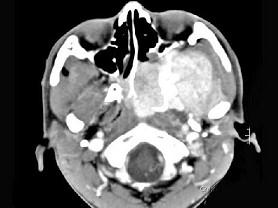

问题 男性,19岁,左侧鼻腔反复出血一年余,CT、MRI扫描如图所示,请选择最可能诊断 ( )

选项 A、鼻咽癌 B、鼻咽部淋巴瘤 C、鼻咽腔脓肿 D、鼻咽部青年纤维血管瘤 E、鼻息肉

答案 D